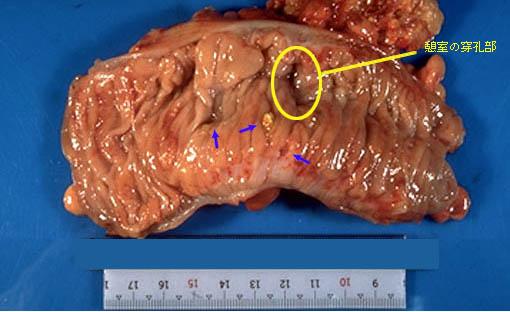

肠憩室周围炎脓肿

乙状结肠憩室周围浓瘤手术病例(东京都台东区浅草消化器研究会病例)

憩室/憩室炎憩室周围浓瘤

部位(按器官分)

大肠/乙状结肠

切除标本(宏观)